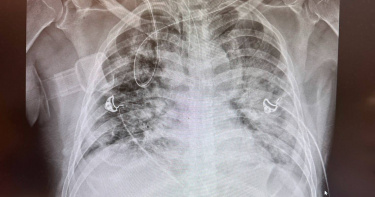

台北市昨(19日)傍晚驚傳恐怖攻擊事件,27歲男子張文先後在捷運台北車站及中山商圈扔煙霧彈、汽油彈及長刀犯案,造成4人死亡、11人受傷,令社會大眾譁然。胸腔科醫師蘇一峰指出,煙霧彈不只嗆人,燃燒後釋放多種化學物質的混合煙霧,吸入恐造成呼吸道與肺部損傷,還有可能延遲3天才惡化,呼籲有接觸者應持續觀察,有不適請及早就醫。蘇一峰醫師在臉書上發文指出,煙霧彈對人體健康具潛在危害。煙霧彈燃燒時會釋放氯化鋅、氧化鋅、六氯乙烷等多種化學成分,吸入後可能造成氣道與肺部損傷。至於吸入性肺損傷的病理變化包括肺泡水腫、纖維母細胞增生,以及肺泡間質膠原蛋白增加,嚴重者可能導致肺纖維化。蘇醫師進一步說明,吸入煙霧彈的影像檢查特徵,電腦斷層(CT)檢查多呈現毛玻璃狀及實質化影像。值得注意的是,肺部水腫可能延遲12至72小時才出現,因此建議曾大量接觸煙霧的人應持續觀察,以防延遲性呼吸道併發症。貼文底下,有不少民眾也紛紛感慨,「台灣社會真的病了!好令人難過的一夜」、「感謝蘇醫師仗義的解說,一般人根本不以為然」、「學到了,有吸到煙霧的人真的要注意身體變化」。昨日的恐怖攻擊事件,據警方調查,嫌犯張文先在捷運台北車站M7出口B1通道點燃疑似自製燃燒物,並投擲煙霧彈製造混亂,隨後持刀攻擊試圖制止的余姓男子,刀刃從左肩刺入,並捅破左肺直達左心房,造成余男當場失去生命跡象,經送醫搶救仍不治。張嫌隨後轉往中山商圈,在北捷中山站外投擲煙霧彈後,再朝蕭姓機車騎士頸部猛刺1刀,傷者頓時血流如注,即便救護人員及時將其送醫,仍宣告不治。張男過程中似乎一度察覺有人追趕,隨後跑進誠品生活南西店,搭乘手扶梯到2樓並再度攻擊多名顧客,造成王姓男子失血過多身亡。最後張嫌在警方包圍下墜樓身亡。◎勇敢求救並非弱者,您的痛苦有人願意傾聽,請撥打1995◎如果您覺得痛苦、似乎沒有出路,您並不孤單,請撥打1925